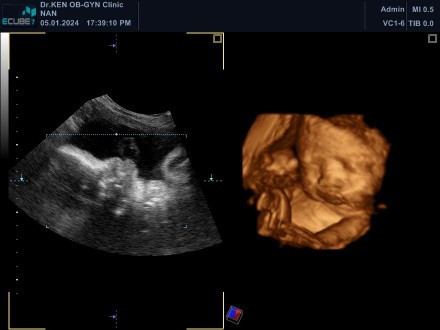

ทีมมีนา67ปีมังกร

กำหนดคลอด9มีนาจ้า บ้านนี้ได้ลูกสาวแม่ๆทีมมีนาแต่ละบ้านได้ลูกชายหรือลูกสาวกันค่ะ